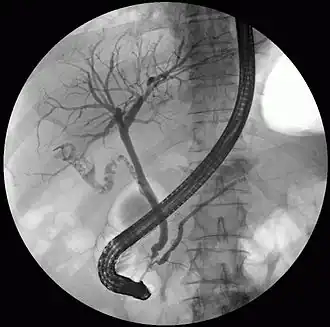

The diagnosis of choledocholithiasis is suggested when the liver function blood test shows an elevation in bilirubin and serum transaminases. Other indicators include raised indicators of ampulla of vater (pancreatic duct obstruction) such as lipases and amylases. In prolonged cases the international normalized ratio (INR) may change due to a decrease in vitamin K absorption. (It is the decreased bile flow which reduces fat breakdown and therefore absorption of fat soluble vitamins). The diagnosis is confirmed with either a magnetic resonance cholangiopancreatography (MRCP), an endoscopic retrograde cholangiopancreatography (ERCP), or an intraoperative cholangiogram. If the patient must have the gallbladder removed for gallstones, the surgeon may choose to proceed with the surgery, and obtain a cholangiogram during the surgery. If the cholangiogram shows a stone in the bile duct, the surgeon may attempt to treat the problem by flushing the stone into the intestine or retrieve the stone back through the cystic duct.

On a different pathway, the physician may choose to proceed with ERCP before surgery. The benefit of ERCP is that it can be utilized not just to diagnose, but also to treat the problem. During ERCP the endoscopist may surgically widen the opening into the bile duct and remove the stone through that opening. ERCP, however, is an invasive procedure and has its own potential complications. Thus, if the suspicion is low, the physician may choose to confirm the diagnosis with MRCP, a non-invasive imaging technique, before proceeding with ERCP or surgery.